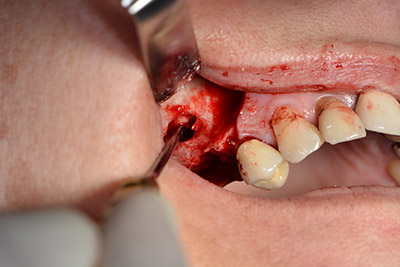

Im nächsten Schritt wird die Sinusbodenelevation mit simultaner Implantation durchgeführt. Für die bukkale Fensterung der Kieferhöhlenwand gibt es auch hier bei der Implantmed an der ersten Position eine Voreinstellung.

Mit 35.000/min wird das Fenster angelegt und anschließend die Schneidersche Membran nach kranial präpariert. (Abb. 13 bis 14).